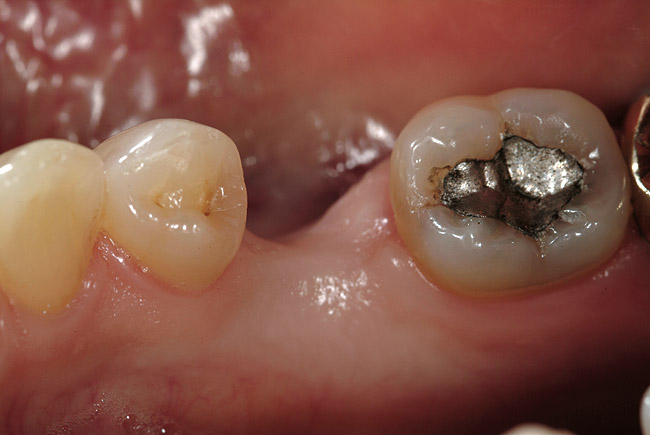

In vitro studies have demonstrated that the use of unidirectional glass-fiber reinforcement in the connector areas of FPDs contributes to significant composite reinforcement.29,36-38,66-68 Similar findings have been reported with a leno-weave UHMWPE and triaxial weave UHMWPE fiber.20,33,36 Fiber-reinforcing materials used by a dental laboratory are either resin pre-impregnated glass fibers, pre-polymerized composite resin surrounding glass fibers, biaxial braid UHMWPE, leno-weave UHMWPE, or a triaxial weave UHMWPE (Table 3). Typically, the preparation designs for the abutment teeth are inlay or onlay preparations (Figure 6A, Figure 6B, Figure 6C, Figure 6D). They are highly successful and can provide the patient with clinical service for more than 5 to 10 years.69 These restorations must be cemented using an adhesive resin technique with resin cements. Both etch-and-rinse adhesives with a self-cure or dual-cure composite resin cement or with a self-adhesive resin cement are indicated for cementing these restorations (Figure 7).36-38,70 Also, fiber-reinforcing materials are being used by dental laboratories in the fabrication of provisional restorations to reinforce and strengthen acrylic and composite-resin provisional materials.15,40,71